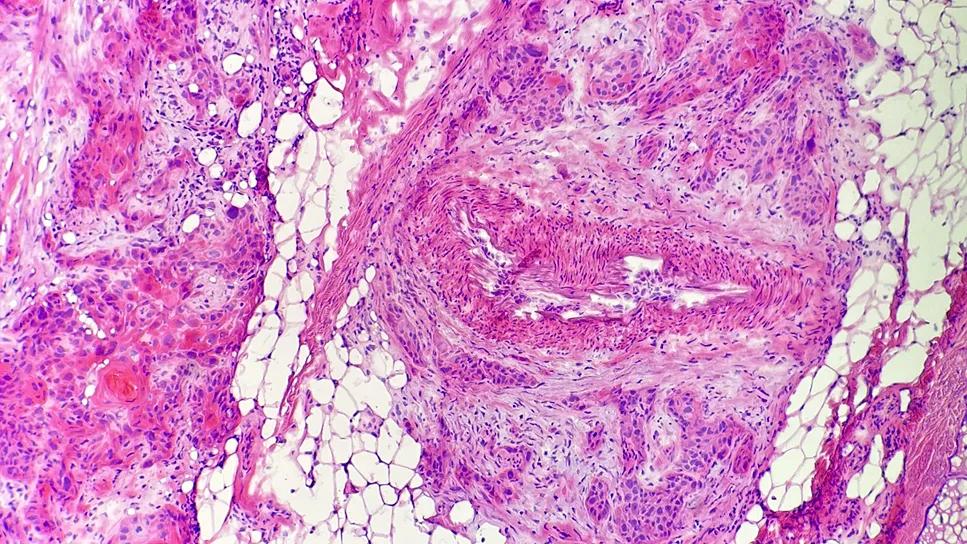

LVI can be elusive and difficult to identify on histopathology. Typically, Mohs surgeons check the edges of the excision of a cSCC tumor to confirm they’ve removed all abnormal cells, but LVI may be at the center of the tumor (i.e., the nonmarginal skin) and therefore may be missed using this approach.

“If we don't know that squamous cell carcinoma has invaded the blood or lymphatic vessels, we're not going to be prompted to do imaging or lymph node sampling,” says Dr. Vidimos. “We’ll have a false sense of security that the cancer is all out, when LVI could be lurking in the nonmarginal tissue, which can portend a more aggressive tumor.”

Proactively looking for LVI. At Cleveland Clinic, Mohs surgeons send a sample of the nonmarginal tissue of high-risk CSCC tumors to pathology to check for concerning features such as LVI and PNI that may prompt additional imaging, adjunctive treatment and closer follow up. If further treatment is warranted, the patient may receive adjuvant radiation or immunotherapy following surgery based on imaging and pathology of metastases.